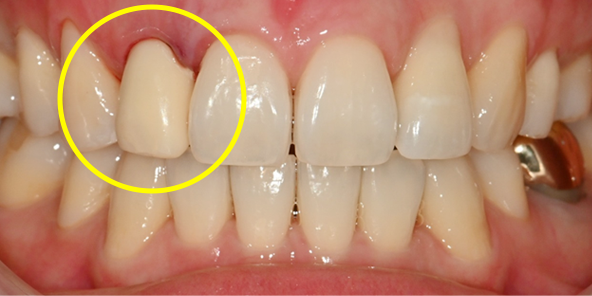

Final Implant Results

BEFORE/AFTER

BEFORE

AFTER